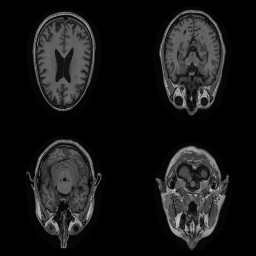

| Original | Renderings after de-identification | Original | MRI slices after de-identification | ||||||

| CP-GAN | FACE MASK | DEFACE | QUICKSHEAR | CP-GAN | FACE MASK | DEFACE | QUICKSHEAR | ||

Benchmark De-Identification Methods. We compare our result with three publicly available and widely-established methods for de-identification of MRI head scans, depicted in Figure 3. All methods have in common that they (1) are not deep-learning-driven, (2) require no additional training and (3), are used on a day-to-day basis in neuroscience and clinical research. All procedures were applied with default settings on images of resolution . The methods include QUICKSHEAR [Schimke et al.(2011)Schimke, Kuehler, and Hale], FACE MASK [Milchenko and Marcus(2013)], and DEFACE [Bischoff-Grethe et al.(2007)Bischoff-Grethe, Ozyurt, Busa, Quinn, Fennema-Notestine, Clark, Morris, Bondi, Jernigan, Dale, Brown, and Fischl]. Descriptions of the methods are provided in the Appendix. We also include MRI WATERSHED [Ségonne et al.(2004)Ségonne, Dale, Busa, Glessner, Salat, Hahn, and Fischl], a skull-stripping method that removes everything except the brain.